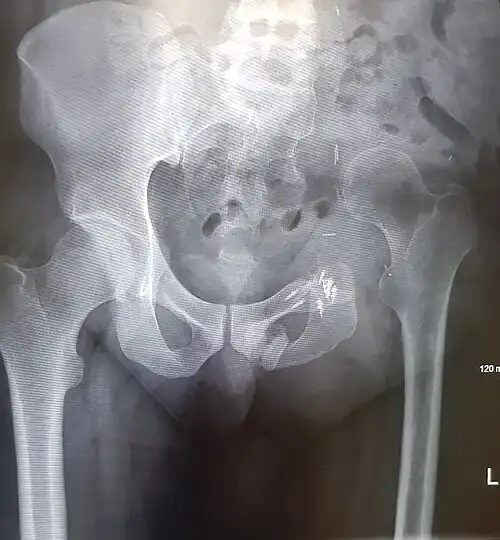

An x-ray of a limb-sparing hemipelvectomy on the left side of a male pelvis taken one month after surgery. -

An x-ray of the same pelvis taken eighteen months after surgery highlighting the femur migration to its final resting place.